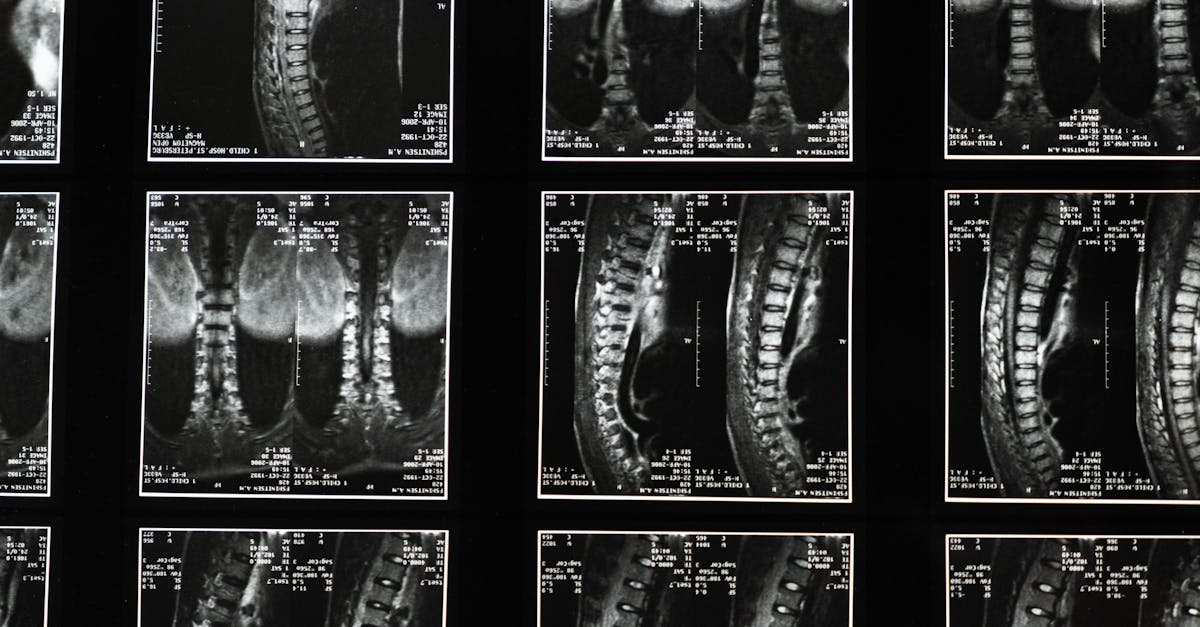

Reposant sur des principes scientifiques, la décompression neurovertébrale utilise la traction contrôlée de la colonne vertébrale pour réduire la pression exercée sur les disques intervertébraux. En assouplissant les vertèbres, cette méthode permet d’augmenter l’hydratation de ces derniers, facilitant ainsi leur réparation. En cela, elle représente une alternative précieuse aux interventions chirurgicales, souvent source d’appréhension et de complications pour les personnes âgées.

Dans le cadre de sa pratique, il met en œuvre des thérapies telles que la décompression vertébrale, ainsi que des traitements au laser et par ondes de choc. Ces approches sont conçues pour cibler directement les sources de douleur et améliorer la fonctionnalité du corps. Grâce à son expertise, le Dr. Desforges a pu aider de nombreux seniors à retrouver une meilleure qualité de vie.